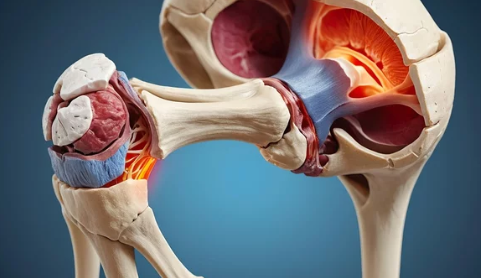

1. 노인 고관절 탈구란?

고관절 탈구는 엉덩이뼈(골반)와 허벅지뼈(대퇴골)가 연결된 관절에서 대퇴골두가 제자리에서 이탈하는 상태를 의미합니다. 이는 보통 강한 외부 충격이나 관절의 퇴행성 변화로 인해 발생합니다.